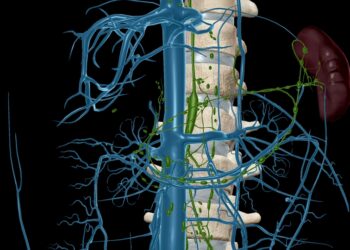

Krūtinės limfmazgiai atlieka svarbų vaidmenį organizmo apsaugos sistemoje, tačiau dėl savo padėties jie dažnai nepastebimi net tada, kai kyla sutrikimų....

Juosmens limfmazgiai – tai imuninės sistemos dalis, sudaryta iš nedidelių, apvalių, pupelės formos darinių, išsidėsčiusių žmogaus kūne įvairiose vietose. Šie...